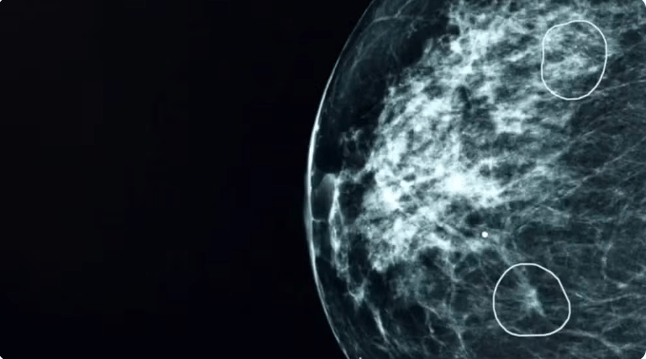

Uma ferramenta de inteligência artificial testada pelo NHS, o serviço público de saúde do Reino Unido, identificou com sucesso pequenos sinais de câncer de mama que não haviam sido detectados por médicos.

A ferramenta, chamada Mia, foi testada em conjunto com médicos do NHS e analisou mamografias de mais de 10 mil mulheres.

Na maioria dos exames, Mia não identificou indícios de câncer, mas sinalizou com sucesso todos aqueles em que havia indícios apontados por médicos antes, além de outros 11 em que os médicos não haviam identificado tumores.

Nos estágios iniciais, o câncer pode ser extremamente pequeno e difícil de detectar.

A BBC acompanhou Mia em ação em um hospital do NHS. Foram mostrados à ferramenta tumores que eram praticamente invisíveis ao olho humano. Mas que, dependendo do tipo, podem crescer e se espalhar rapidamente.

Como seu tumor de 6 mm foi detectado muito precocemente, ela foi operada e precisou apenas de cinco dias de radioterapia.

Pacientes com câncer de mama com tumores menores do que 15 mm quando descobertos têm uma taxa de sobrevivência de 90% nos cinco anos seguintes.